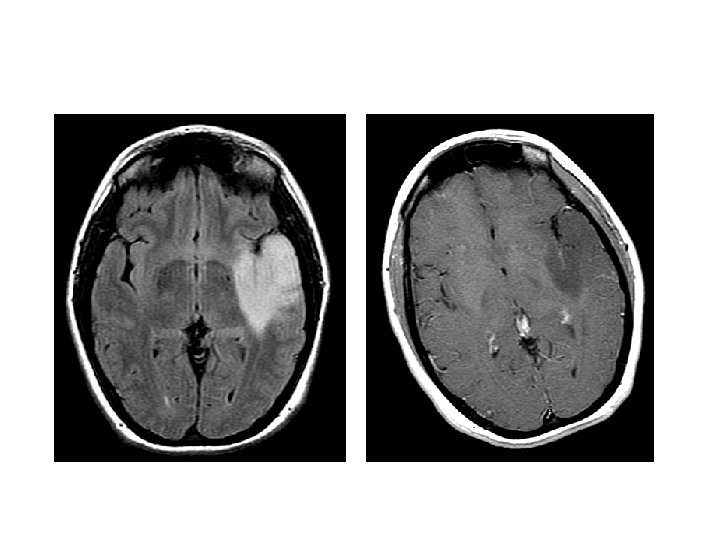

c. Glioblastoma (WHO grade IV) - It has a histologic appearance similar to anaplastic astrocytoma with the additional features of: a. Pseudopalisading necrosis - The neoplastic cells collect along the edges of the necrotic regions a. and /or b. Microvasular proliferation

• Radiologically: Shows contrast enhancement

Patterns of Contrast Enhancement Abscess PCNSL GBM Demyelinating Pseudotumor PXA Cavernoma

Glioblastoma (WHO grade IV)

Glioblastoma Glioblatomas are either: 1. Primary - The patients develop it from the start - Is the most common type of glioblastoma 2. Secondary - Progress from lower grades

- The prognosis for glioblastoma is poor , although the use of newer therapeutic drugs has provided some benefits - With current treatment consisting of resection followed by radiation therapy and chemotherapy, the mean length of survival has increased to 15 months - 25% of such patients are alive after 2 years